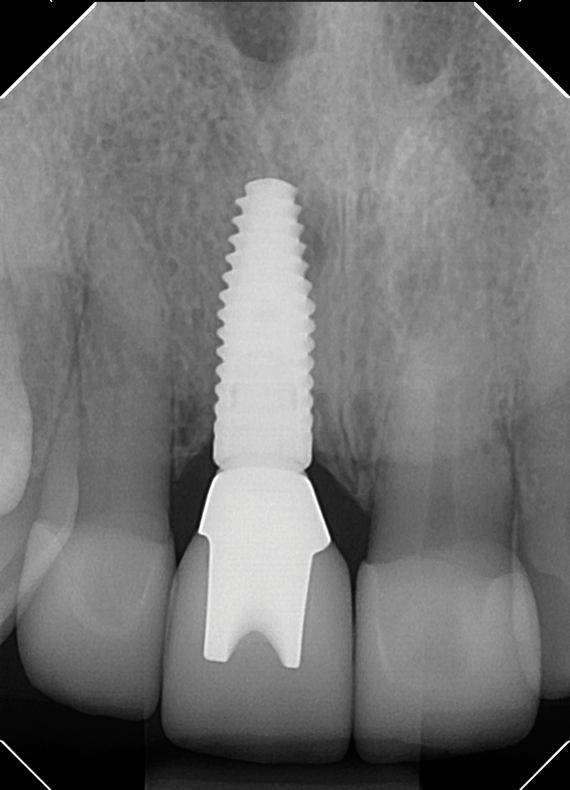

Fig 4. Radiograph of the implant to replace the tooth in Fig 3 (implant placed by David Levine, DDS).

Figure 4